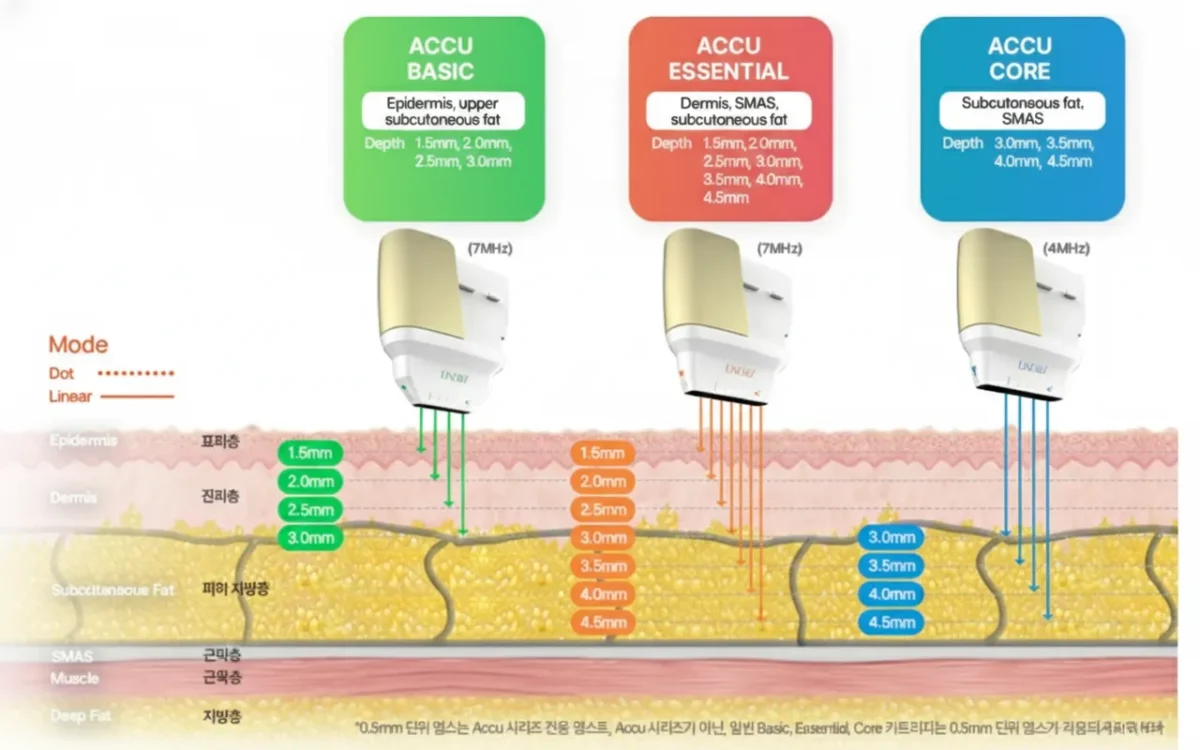

- Linear Z HIFU is delivered into the deep skin fractionally.

- Cause thermal coagulation to SMAS (Superficial Muscular Aponeurotic System), fascia, deep dermis and subcutaneous fibrous tissue

- By wound healing; skin tightening and rejuvenation happens gradually over time